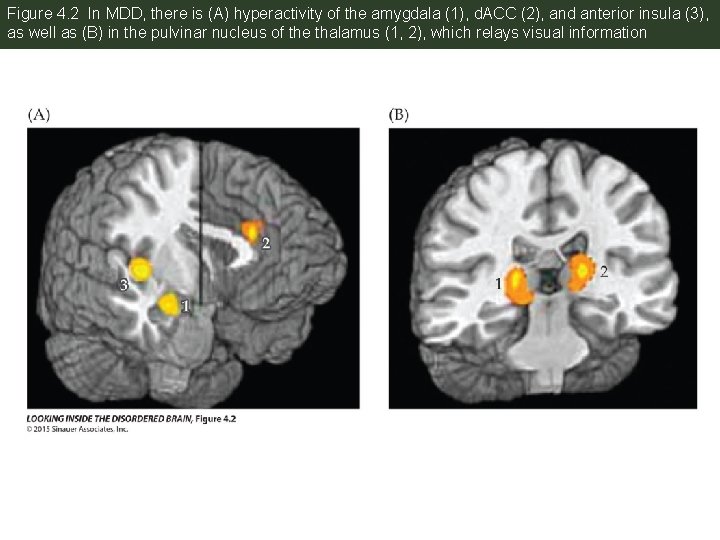

Figure 4. 2 In MDD, there is (A) hyperactivity of the amygdala (1), d. ACC (2), and anterior insula (3), as well as (B) in the pulvinar nucleus of the thalamus (1, 2), which relays visual information